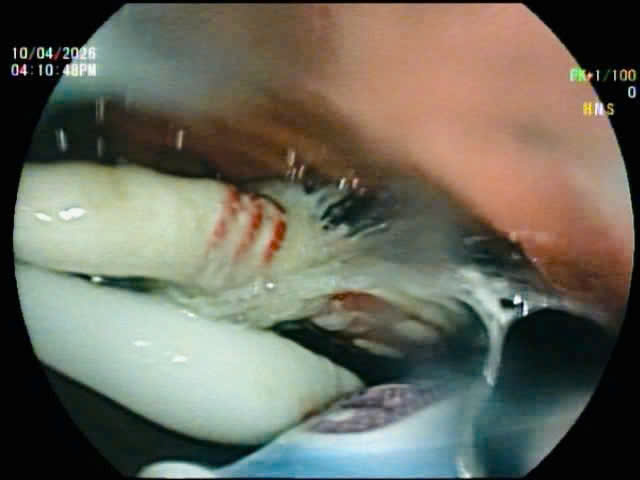

Ngay sau khi tiếp nhận, bệnh nhân được chỉ định nội soi can thiệp. Đội ngũ ê-kíp đã tiến hành gắp thành công toàn bộ 3 dị vật (bàn chải đánh răng dài gần 20cm) ra khỏi đường tiêu hóa. Việc can thiệp diễn ra thuận lợi, không ghi nhận biến chứng.

ThS.BS. Phạm Như Hiển, Phó giám đốc Trung tâm Nội soi, Bệnh viện Trung ương Huế, cho biết đây là trường hợp hiếm gặp khi bệnh nhân nuốt cùng lúc 3 dị vật dài và cứng, có tiềm ẩn nguy cơ cao mắc kẹt trong ống tiêu hóa, gây tổn thương niêm mạc, thủng hoặc tắc nghẽn nếu không được phát hiện và xử trí kịp thời. Dù ca bệnh có tính chất phức tạp, toàn bộ dị vật đã được lấy ra bằng phương pháp nội soi và không cần can thiệp phẫu thuật.

Dị vật được xác định là bàn chải đánh răng bệnh nhân nuốt vào bụng